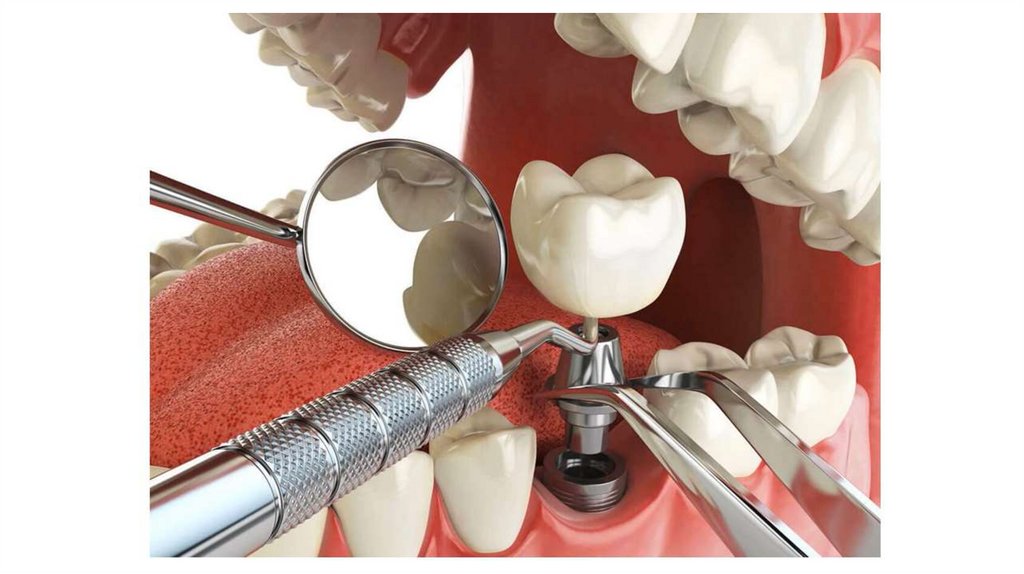

Этапы восстановления дефектов зубных рядов

протезами с опорой на имплантаты

1. Планирование ортопедического лечения

Обследование пациента, выбор ортопедической конструкции КЛКТ

Изготовление навигационного хирургического шаблона

2. Хирургический этап - дентальная имплантация

Одноэтапный протокол

Двухэтапный протокол

Установка имплантата

Установка формирователя десны

3. Ортопедический этап